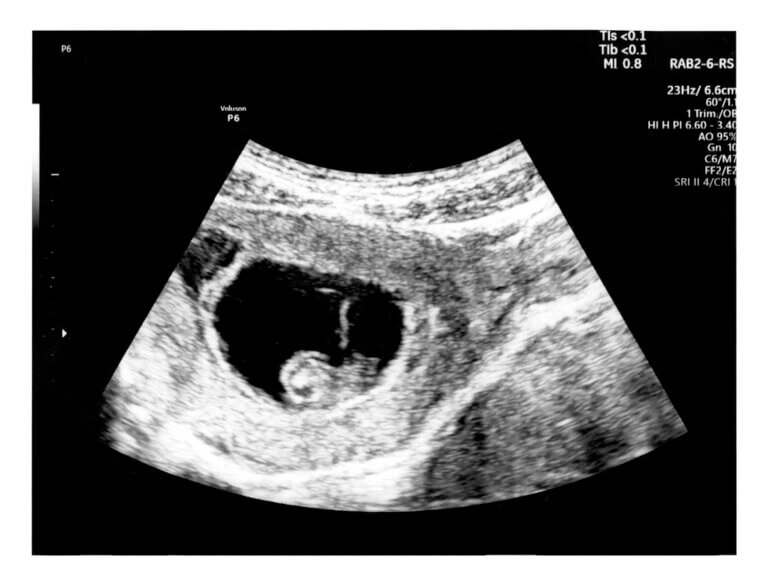

Etapas da gravidez

Seu corpo está mudando semana a semana, enquanto seu bebê cresce e coisas que você nem imagina acontecem. O processo de gestação é maravilhoso, um milagre único que nós iremos explicar em detalhe, de forma prática e fácil de entender para que você aproveite ao máximo esta etapa da sua vida.